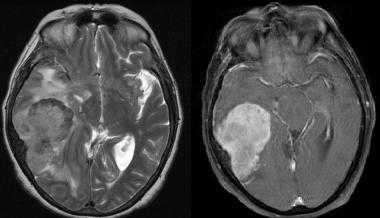

Фалькс-менингиома на МРТ.

А: на Т1-взвешенном МР-изображении отмечается солидное образование, характеризующееся изоинтенсивностью по отношению к твердой мозговой оболочке, инвазией в кость и сдавлением теменных зон коры.

В: На Т1-взвешенном МР-изображении с контрастным усилением видна частично контрастируемая опухоль.

С: На корональном Т2-взвешенном изображении видно изоинтенсивное образование, что соответствует плотной ткани. Такая картина характерна для фибробластных менингиом.

D : На Т1-взвешенном МР-изображении с контрастным усилением визуализируется гиперинтенсивное образование внутри мозгового вещества кости.